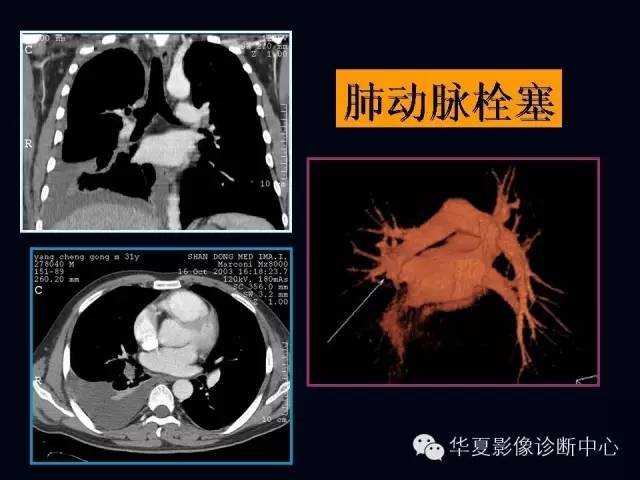

肺部血管性疾病

【PPT】肺部血管性疾病